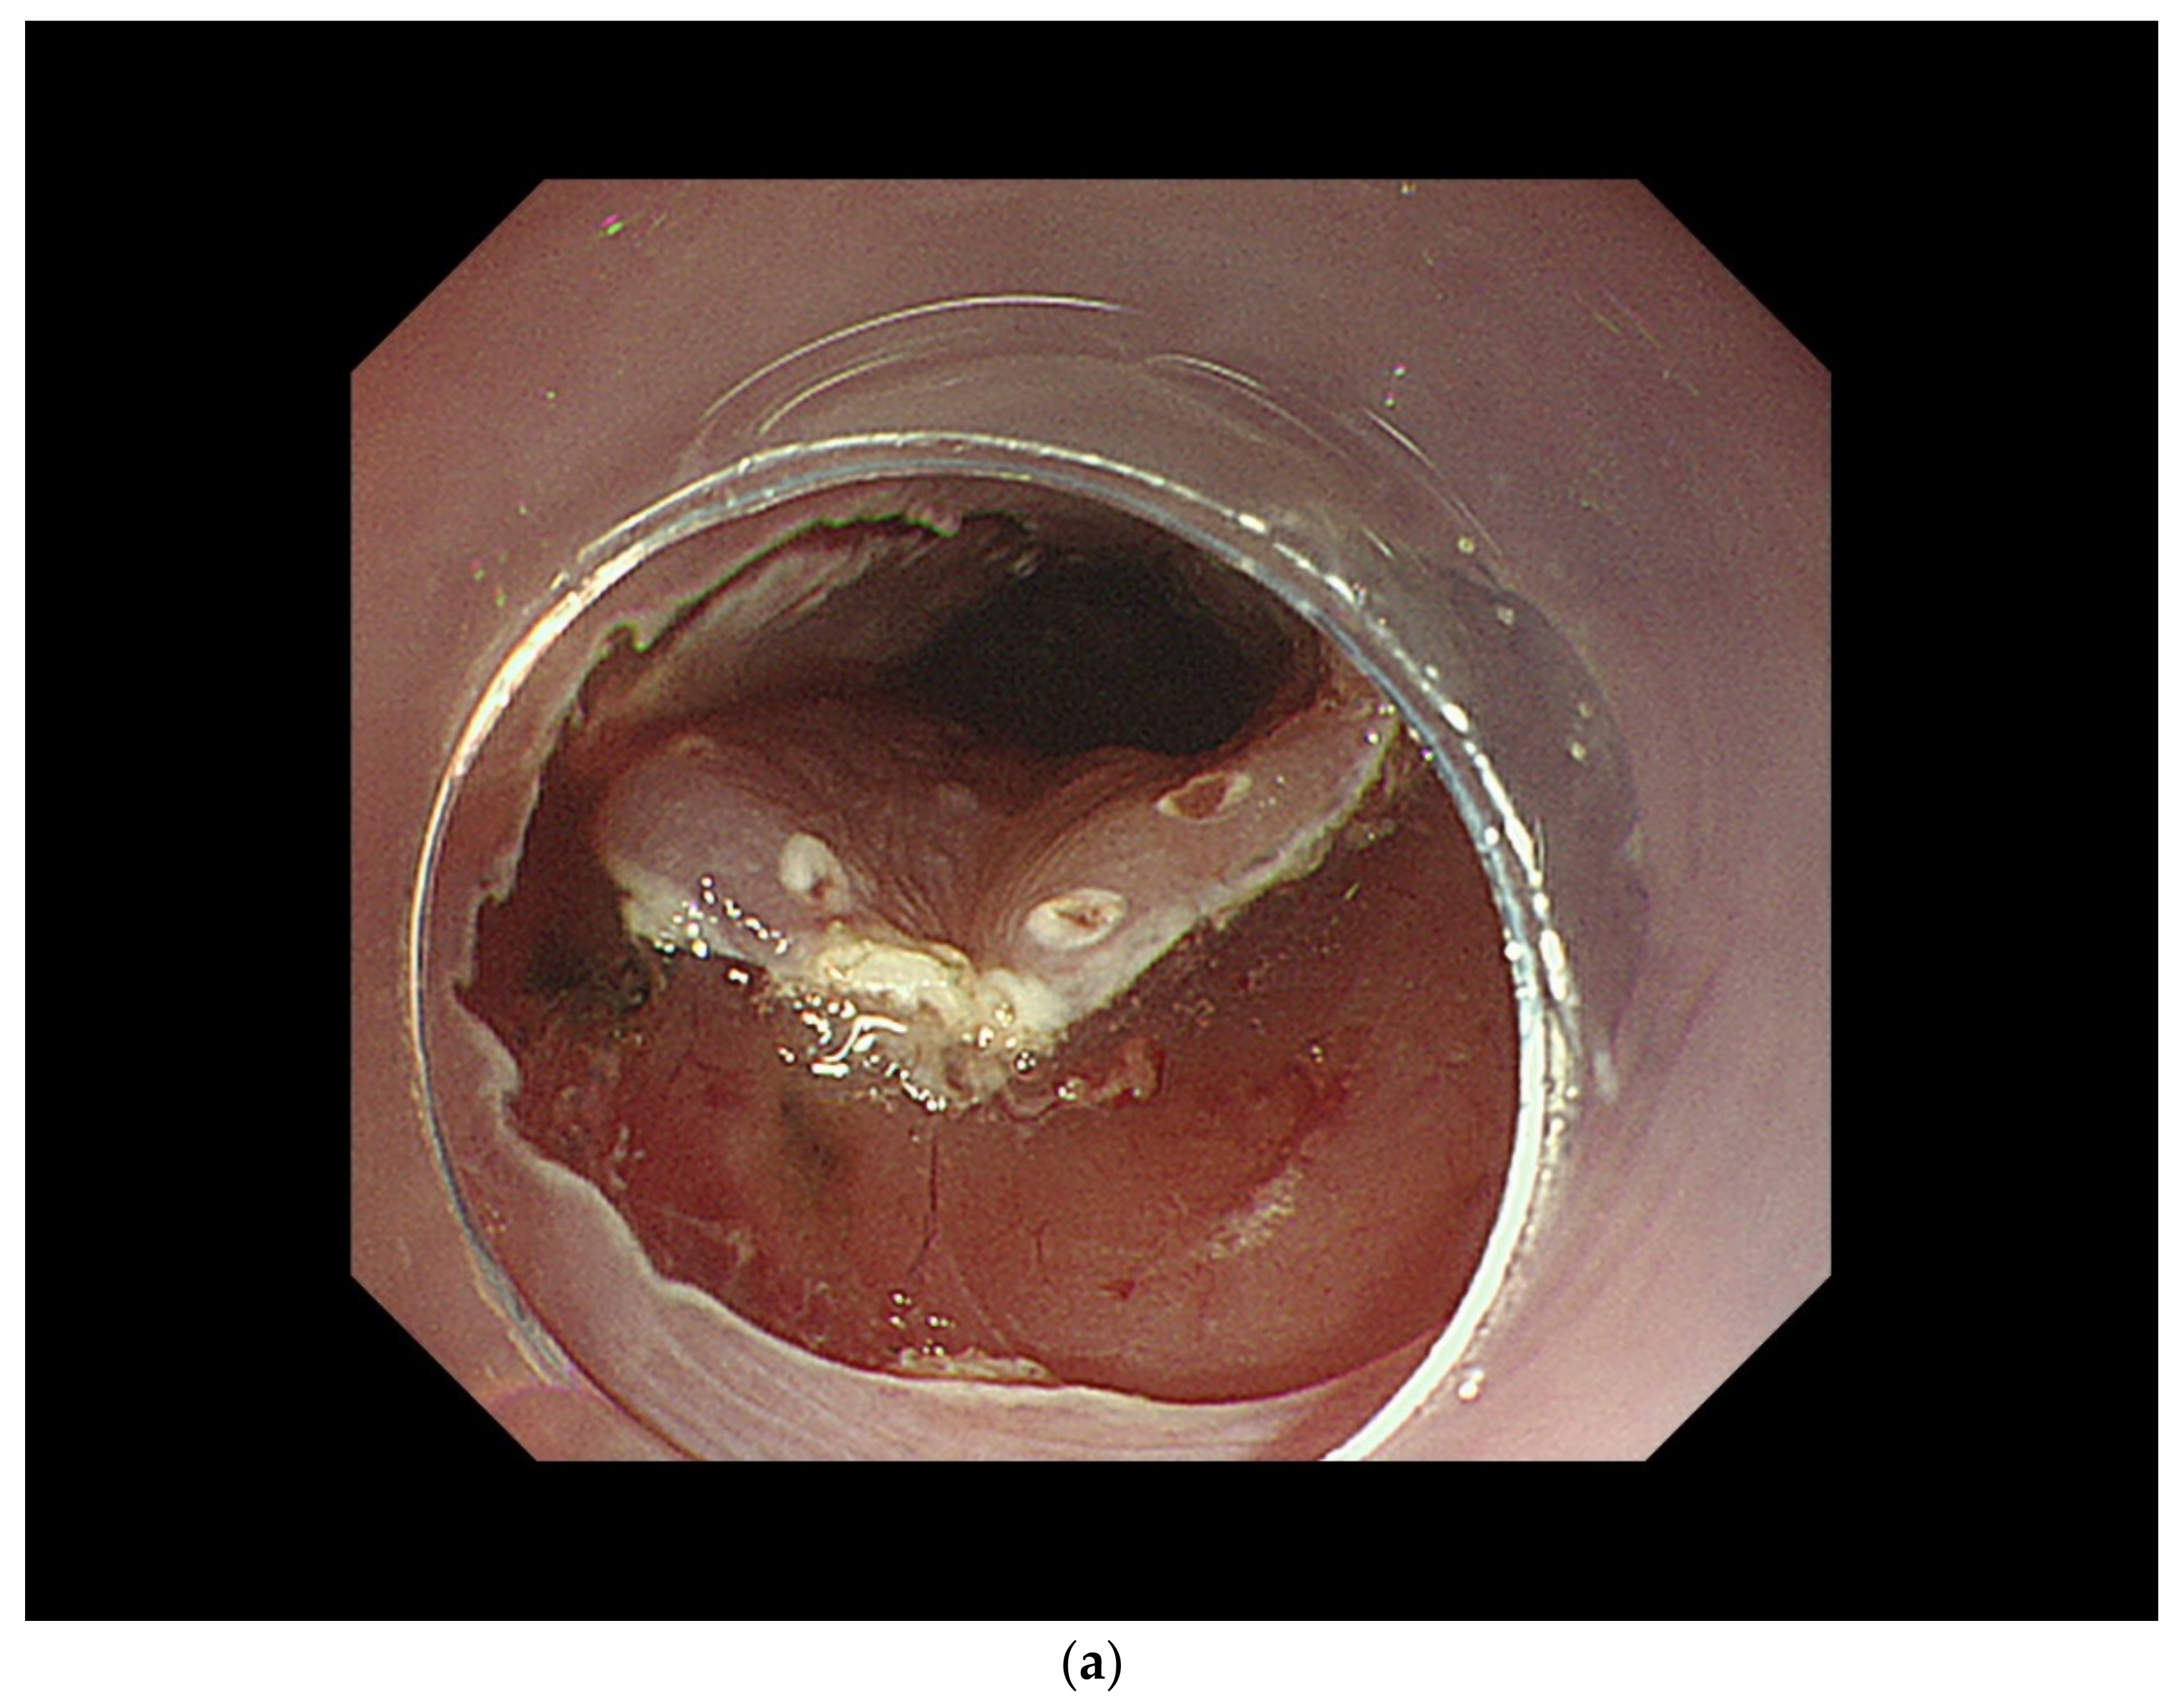

3.2. Diagnosis of Cancer Invasion Depth by White-Light Endoscopy and Magnifying Endoscopy